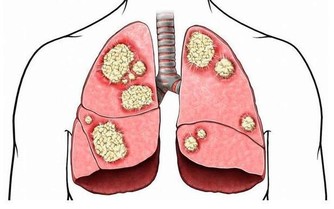

麻疹可能引發嚴重的併發症,如肺炎、腦炎,甚至死亡。未接種疫苗者在接觸麻疹患者後,約90%會感染,顯示出病毒的高傳染性。

接種麻疹疫苗能有效避免因感染麻疹而產生的健康風險,特別是併發症如肺炎和腦炎,這些可能導致長期健康問題甚至死亡。

雖然麻疹疫苗可能導致過敏反應或其他罕見不良反應,但其發生率極低(每百萬劑約1例)。相比麻疹感染引發的嚴重併發症,接種疫苗的風險要小得多。